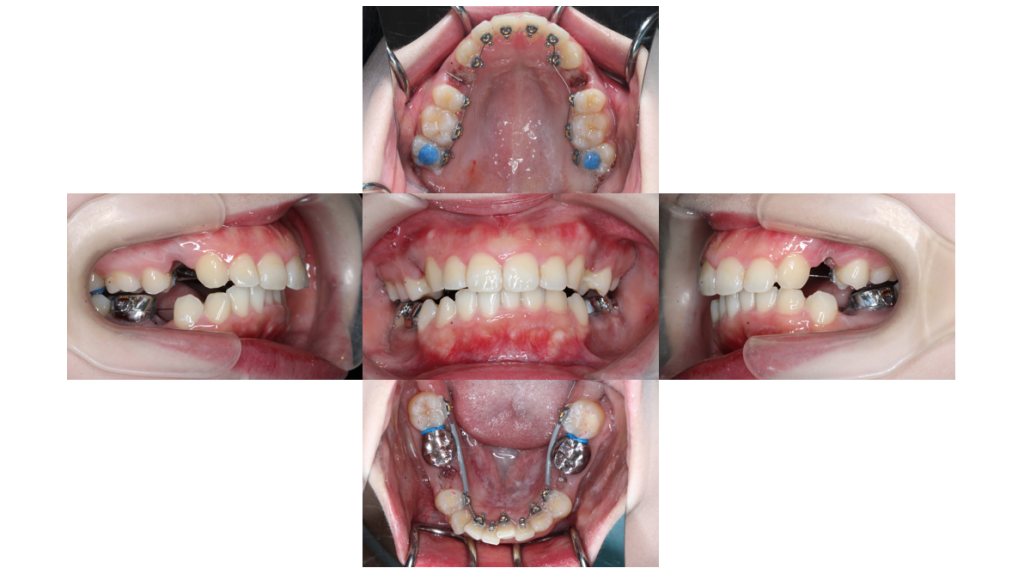

約3ヶ月経過

上顎前突・裏側矯正の症例約3ヶ月経過し、ガタつきが改善されてきました